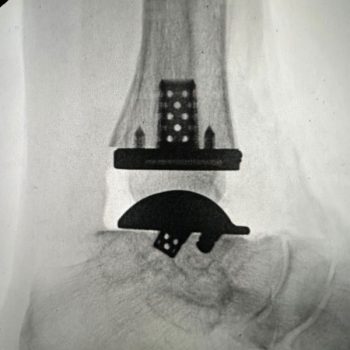

Advita’s Vantage Ankle 3D and 3D+ tibial implants provide surgeons with tibial stem heights from 10 to 30mm and the added benefits of 3D printing. Additive manufacturing creates a surface that mimics the trabecular nature of cancellous bone. Along with the 3D-printed surface, the implants also feature spiked pegs and a tall sharp central cage, with growing diameters, to aid with initial fixation.

“After several years of developing the 3D+ tibial component with the outstanding Advita engineers and other design team surgeons, Jim, Jim [Lachman] and I are pleased how the new tibial components and instrumentation seamlessly melded with the existing talar component options. The additive manufacturing, and the press-fit pegs and augmented central cage afford satisfying initial tibial component stability. Particularly exciting is how the intuitive instrumentation allows for reliable and reproducible insertion of a stemmed tibial component through a routine anterior ankle surgical approach.”